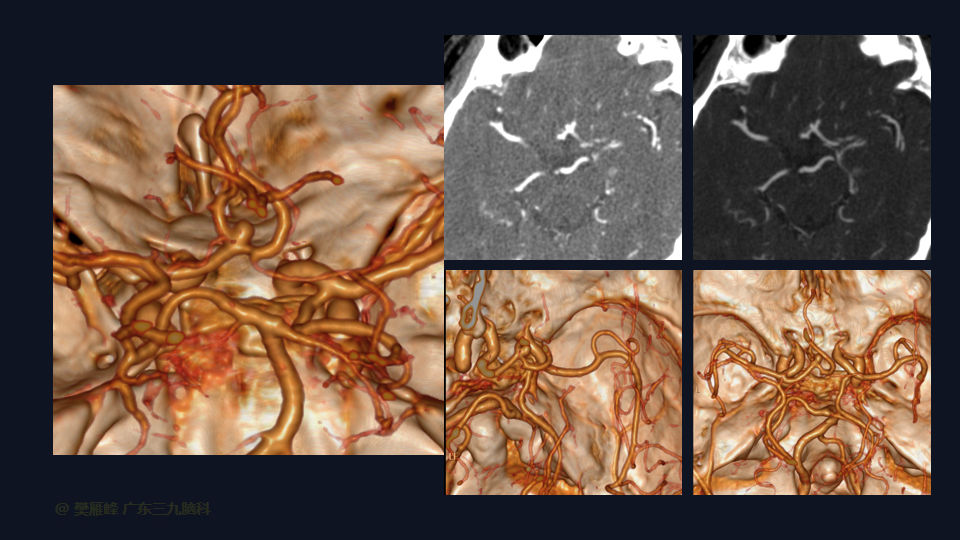

在这个二维手术视频中,展示了一种经翼点入路显微夹闭未破裂的前交通动脉瘤的方法。患者是一名61岁的男性,发现前交通动脉瘤1年较前增大,神经影像学显示前交通动脉大小约为3.6×3.3mm的囊状突起影。他接受了开颅手术夹闭动脉瘤的方法,术中血管造影显示动脉瘤完全夹闭。术后无新发神经功能。我们展示了细微的动脉分离技术和动脉瘤夹闭技术的细微差别和技术要点,以及手术技术。